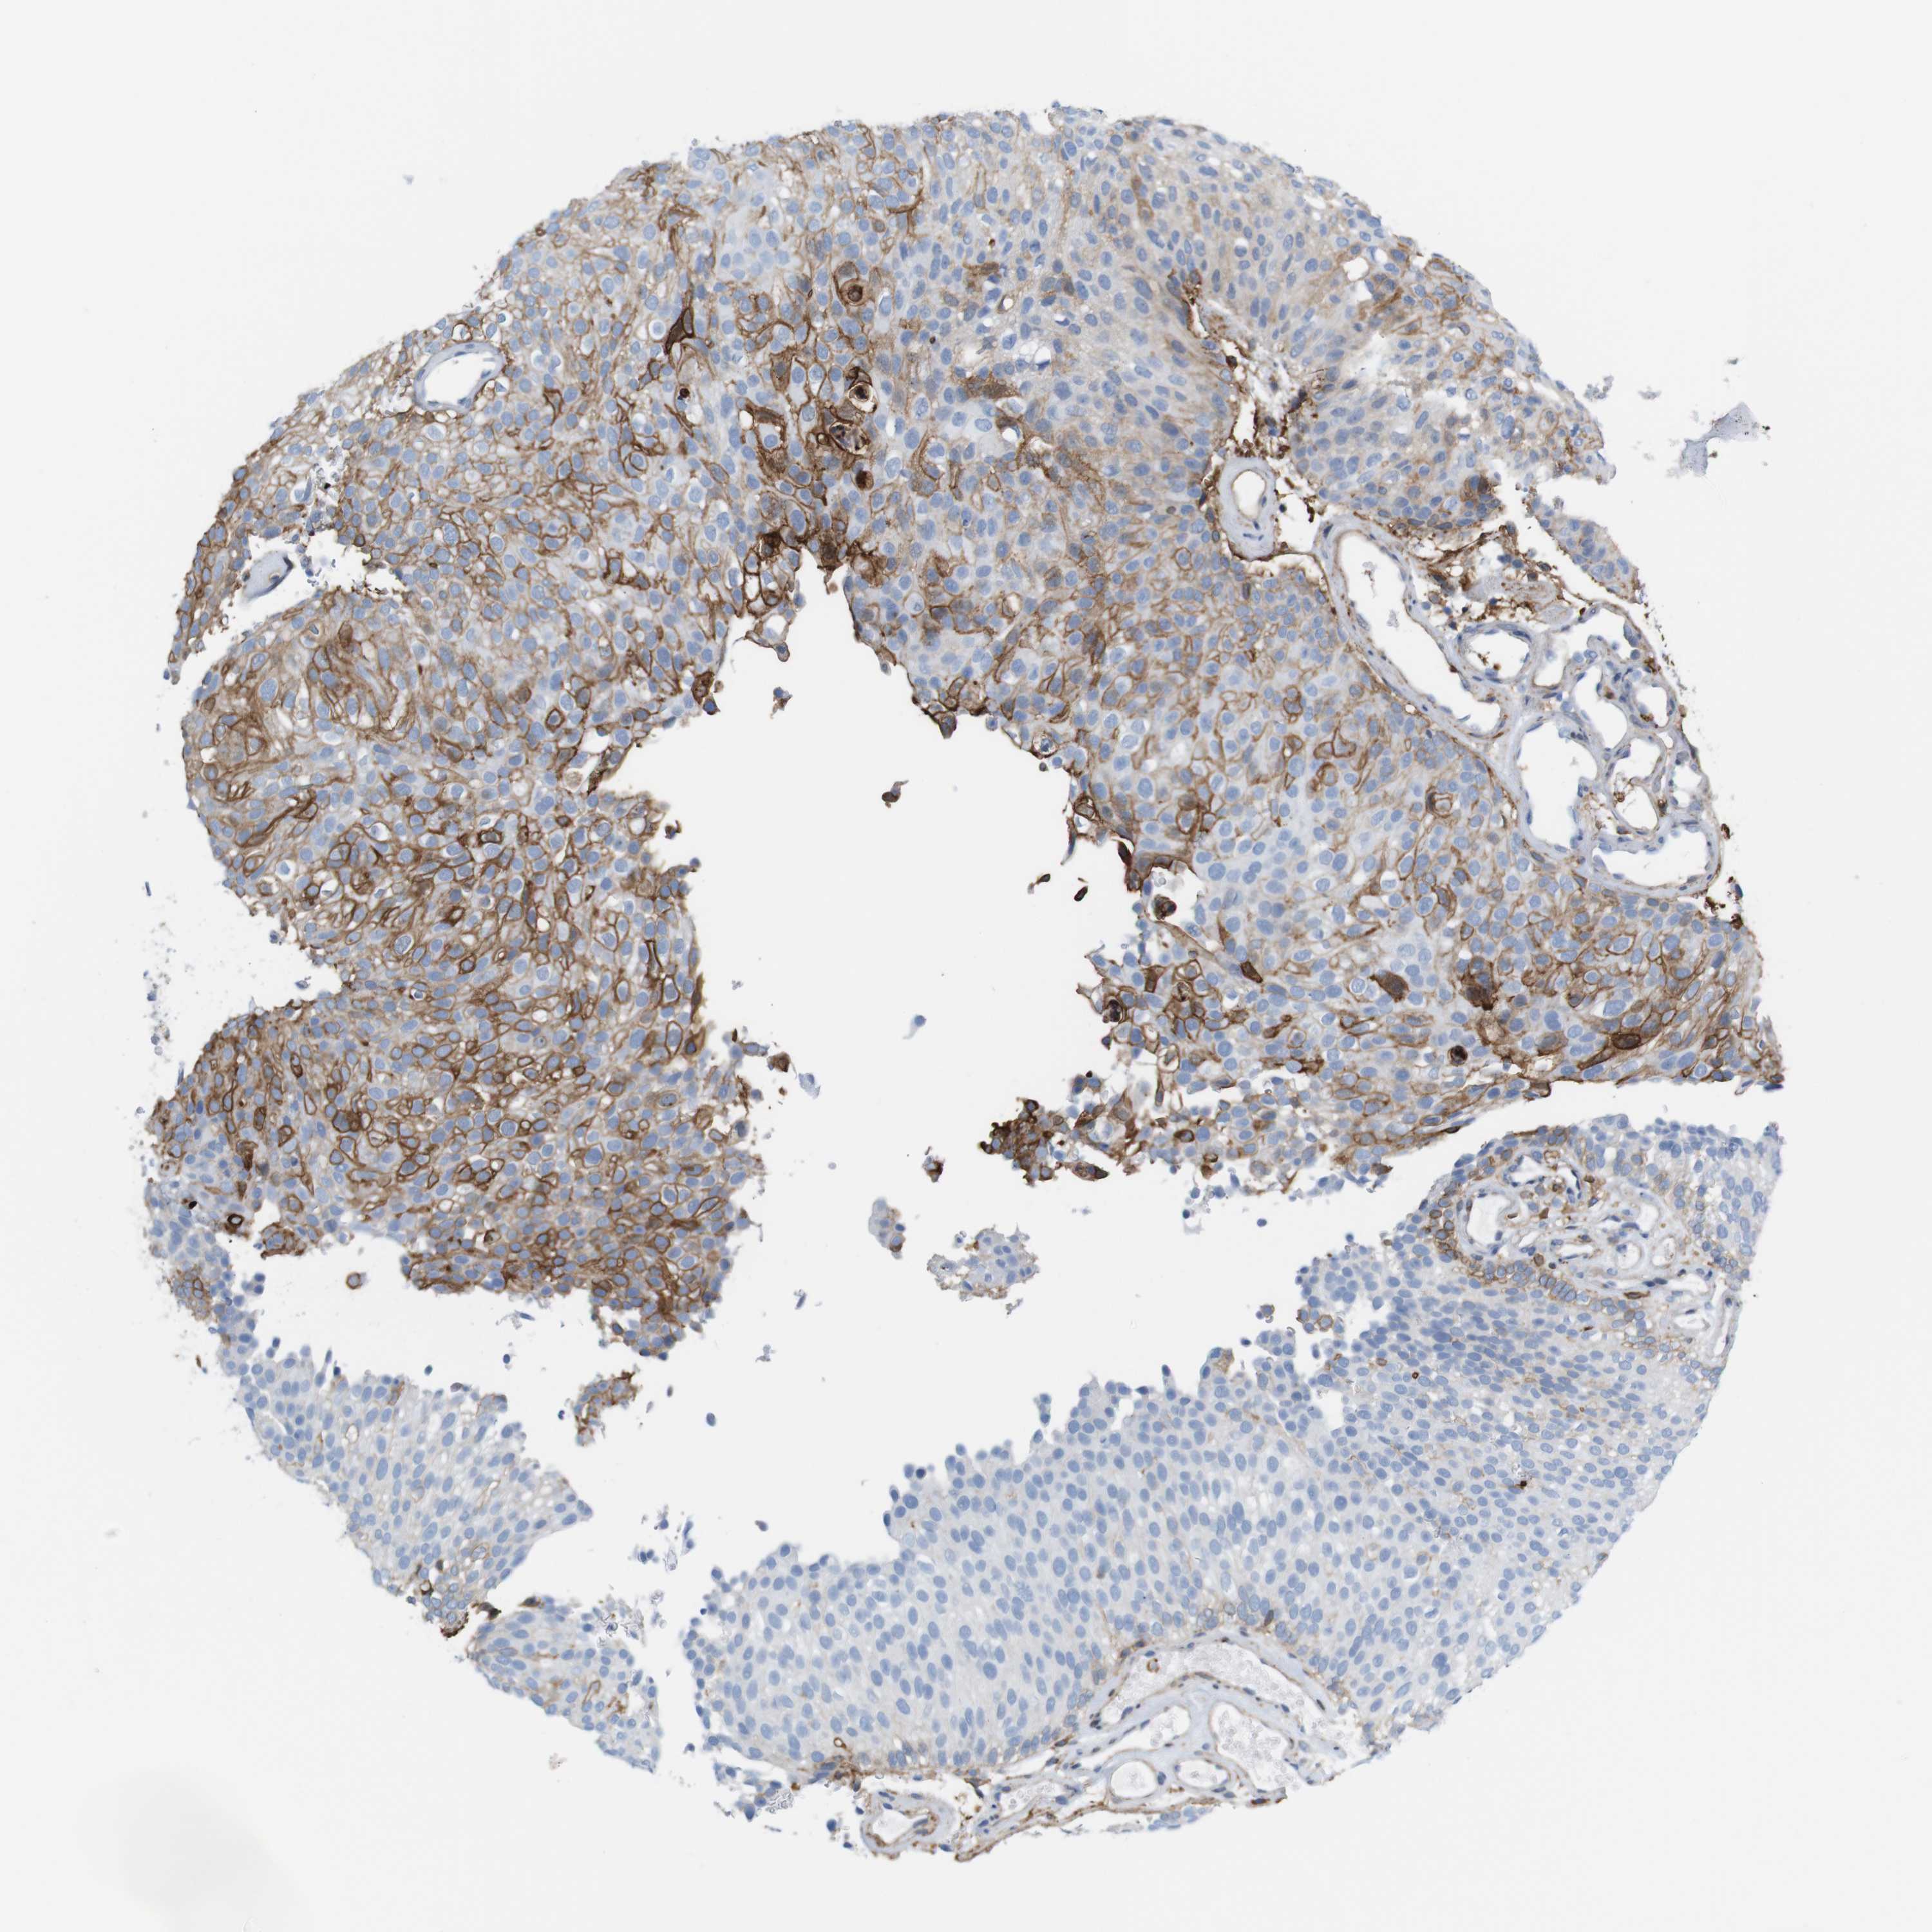

UROTHELIAL CANCER - Protein expressioni

A mouse-over function shows sample information and annotation data. Click on an image to view it in a full screen mode. Samples can be filtered based on level of antibody staining by selecting one or several of the following categories: high, medium, low and not detected. The assay and annotation is described here.

Note that samples used for immunohistochemistry by the Human Protein Atlas do not correspond to samples in the TCGA dataset.

Antibody stainingi

Antibody staining in the annotated cell types in the current human tissue is reported as not detected, low, medium, or high, based on conventional immunohistochemistry profiling in selected tissues. This score is based on the combination of the staining intensity and fraction of stained cells.

Each image is clickable and will lead to virtual microscopy that enables deeper exploration of all samples and also displays staining intensity scores, fraction scores and subcellular localization as well as patient and tissue information for each sample.

HPA011271

HPA011272

CAB013023

CAB035987

CAB058693

CAB080415

Staining

High

Medium

Low

Not detected

Intensity

Strong

Moderate

Weak

Negative

Quantity

>75%

75%-25%

<25%

None

Location

Nuclear

Cytoplasmic/membranous

Cytoplasmic/membranous,nuclear

Urothelial carcinoma, Low grade

Urothelial carcinoma, High grade

Urothelial carcinoma, NOS